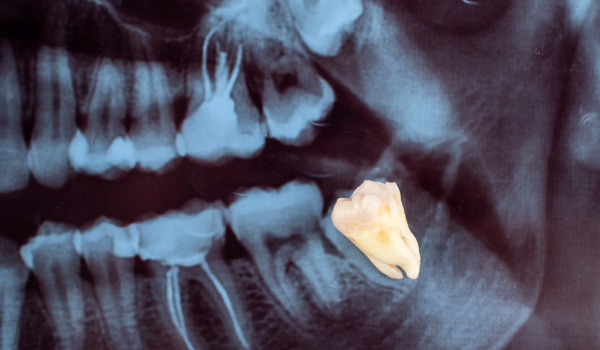

Кваліфіковане видалення третіх молярів

Блок 1. Кваліфіковане видалення третіх молярів

• Урок 1 - Кваліфіковане видалення третіх молярів

- Показання до видалення - видаляти чи залишати до появи скарг? В якому віці найкраще спланувати оперативне втручання?

- Методика атипового видалення зубів мудрості.